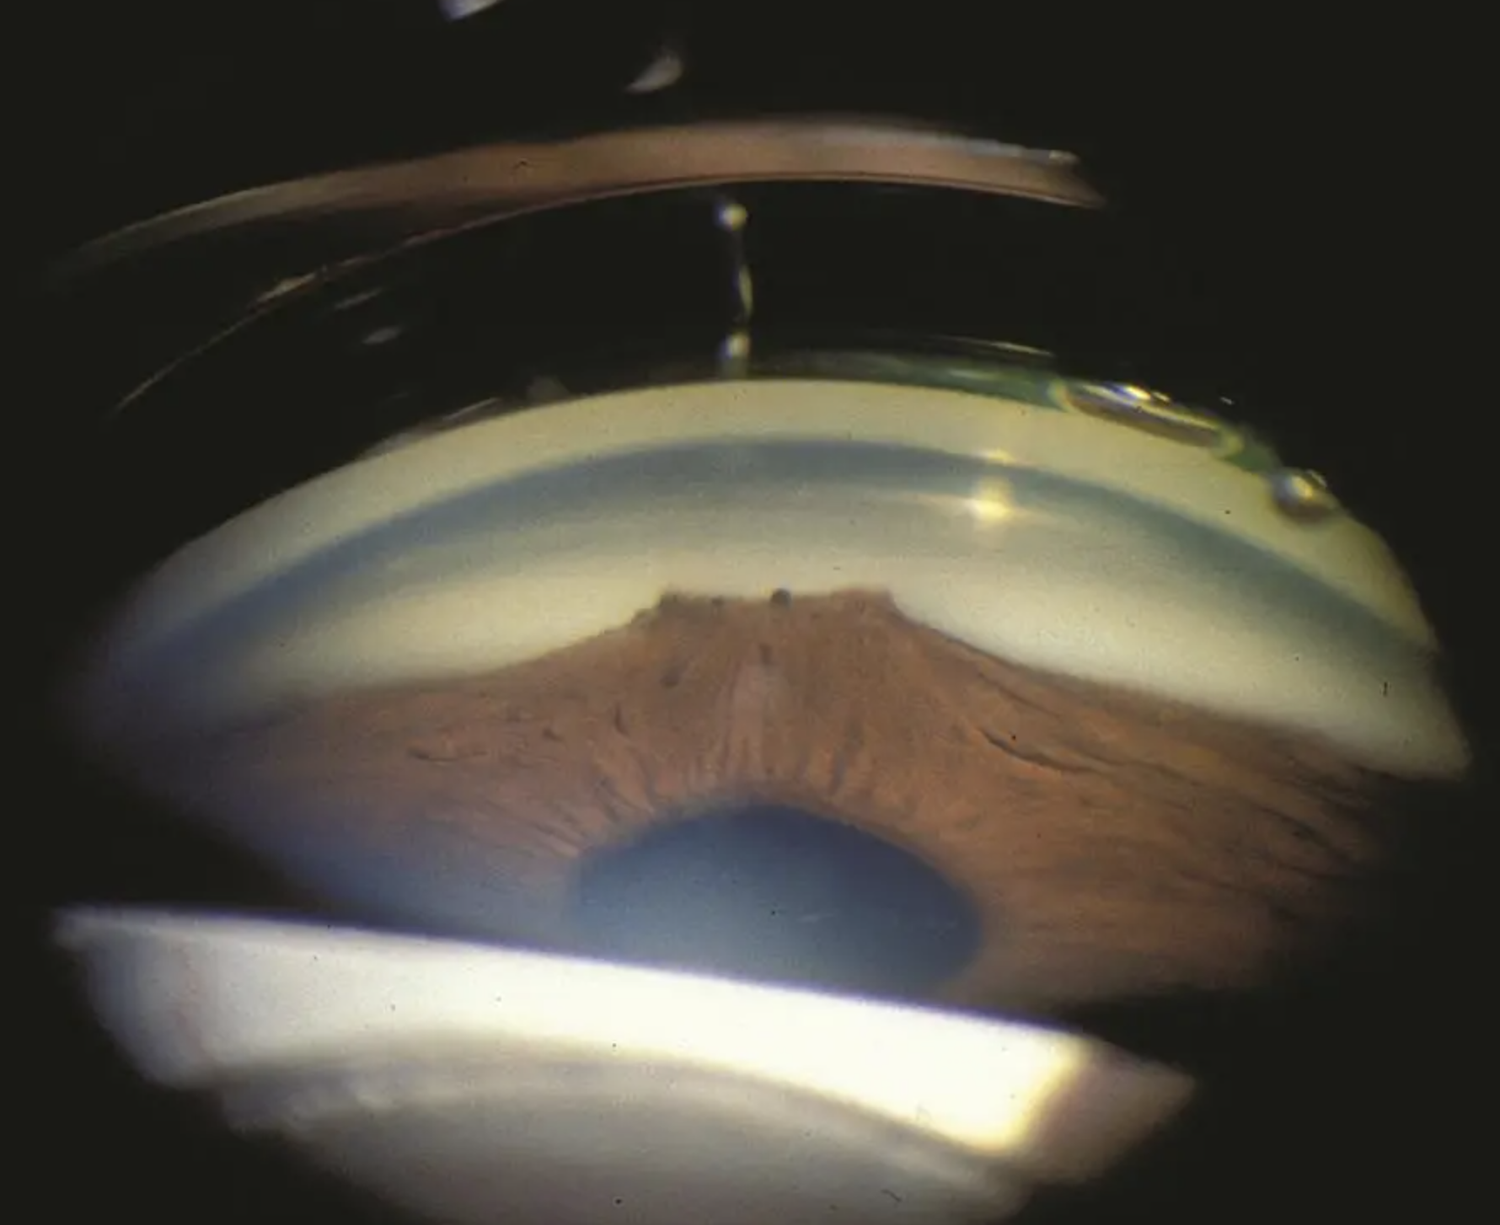

First step: determine if you can see structures. Here’s a mnemonic, from posterior to anterior:

I Can’t See This Sh…tuff.

- Iris

- Ciliary body

- Scleral spur

- Trabecular meshwork

- Schwalbe’s line